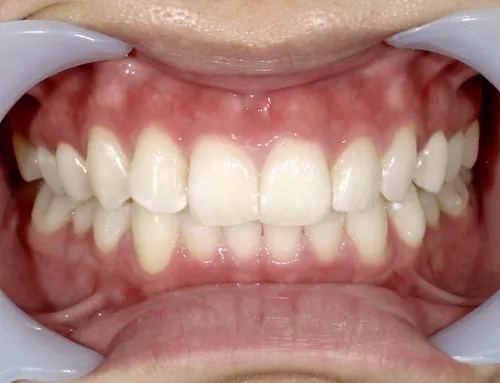

歯科の医療ホワイトニング

痛くない・しみないのに、45分で白くなる。